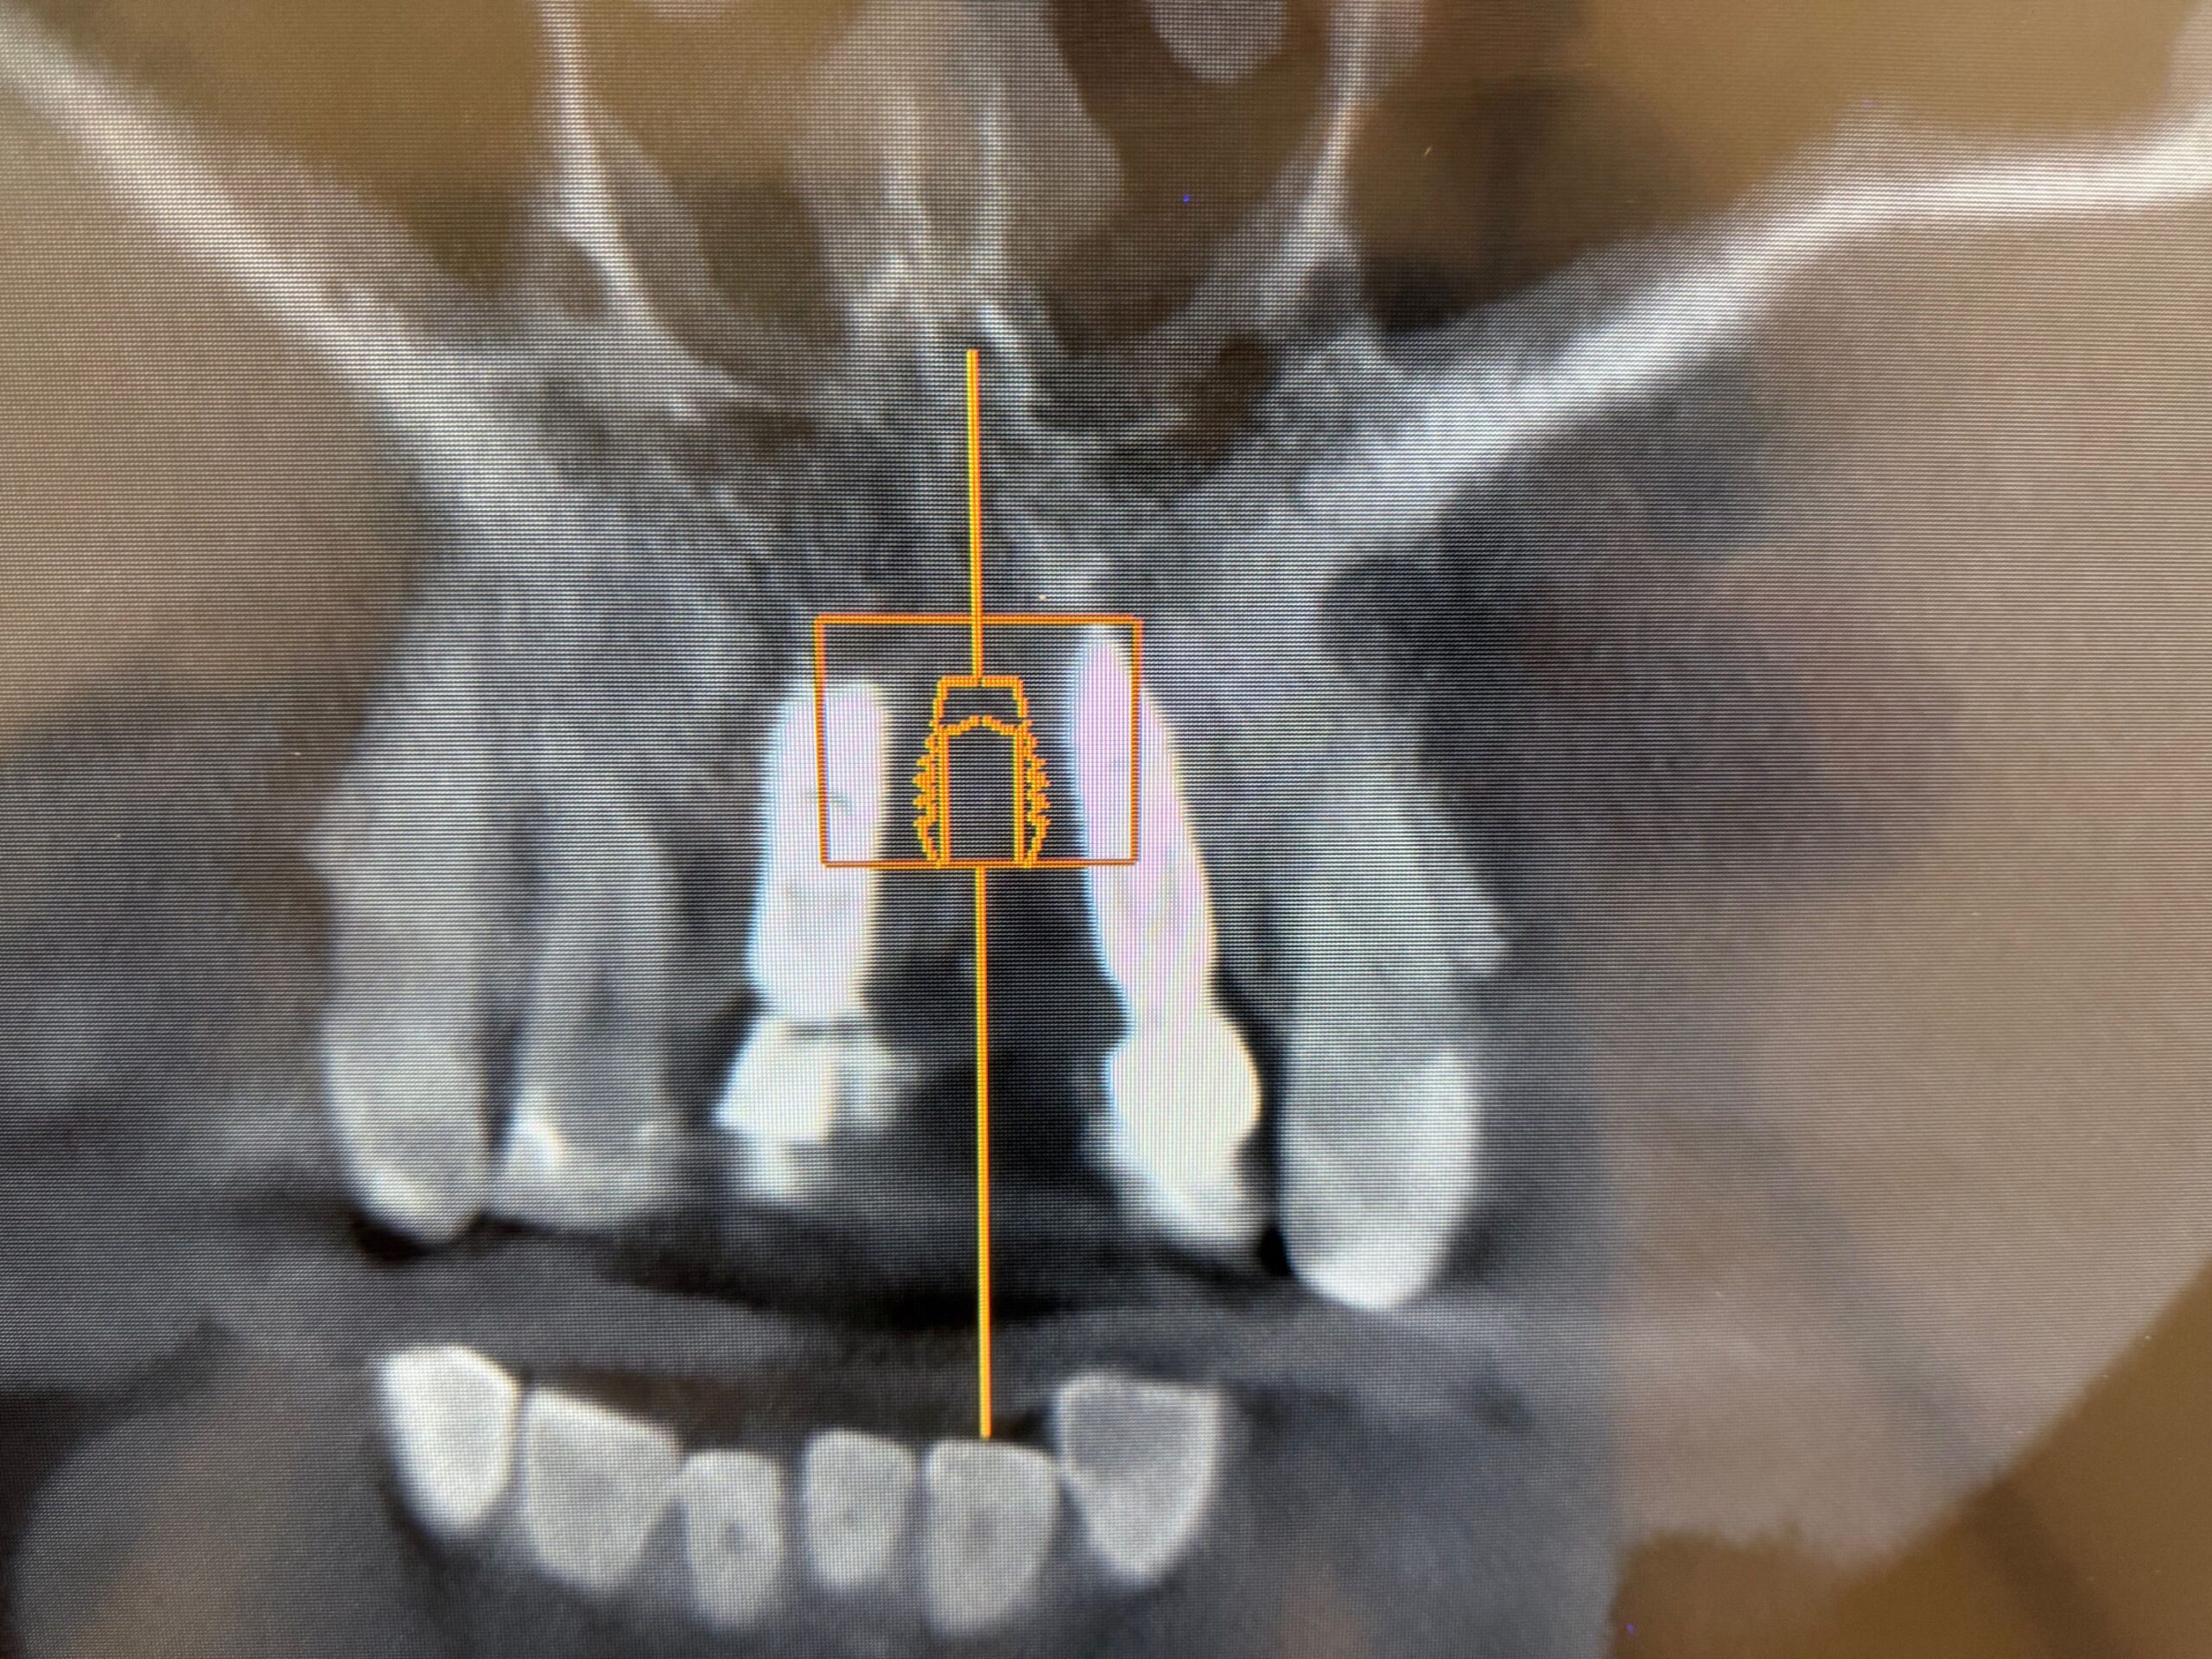

バイコンインプラントの神仕様

バイコンインプラントは、インプラント間距離が1mm程度あれば

打ち込むところに特殊性があります。

過度に骨を圧迫しないで埋入するので、隣のインプラントと近くて

他社製品を使って、この場所にインプラントをすることは不可能で

ちなみにこの他社インプラント間の埋入は、初めてのケースです。